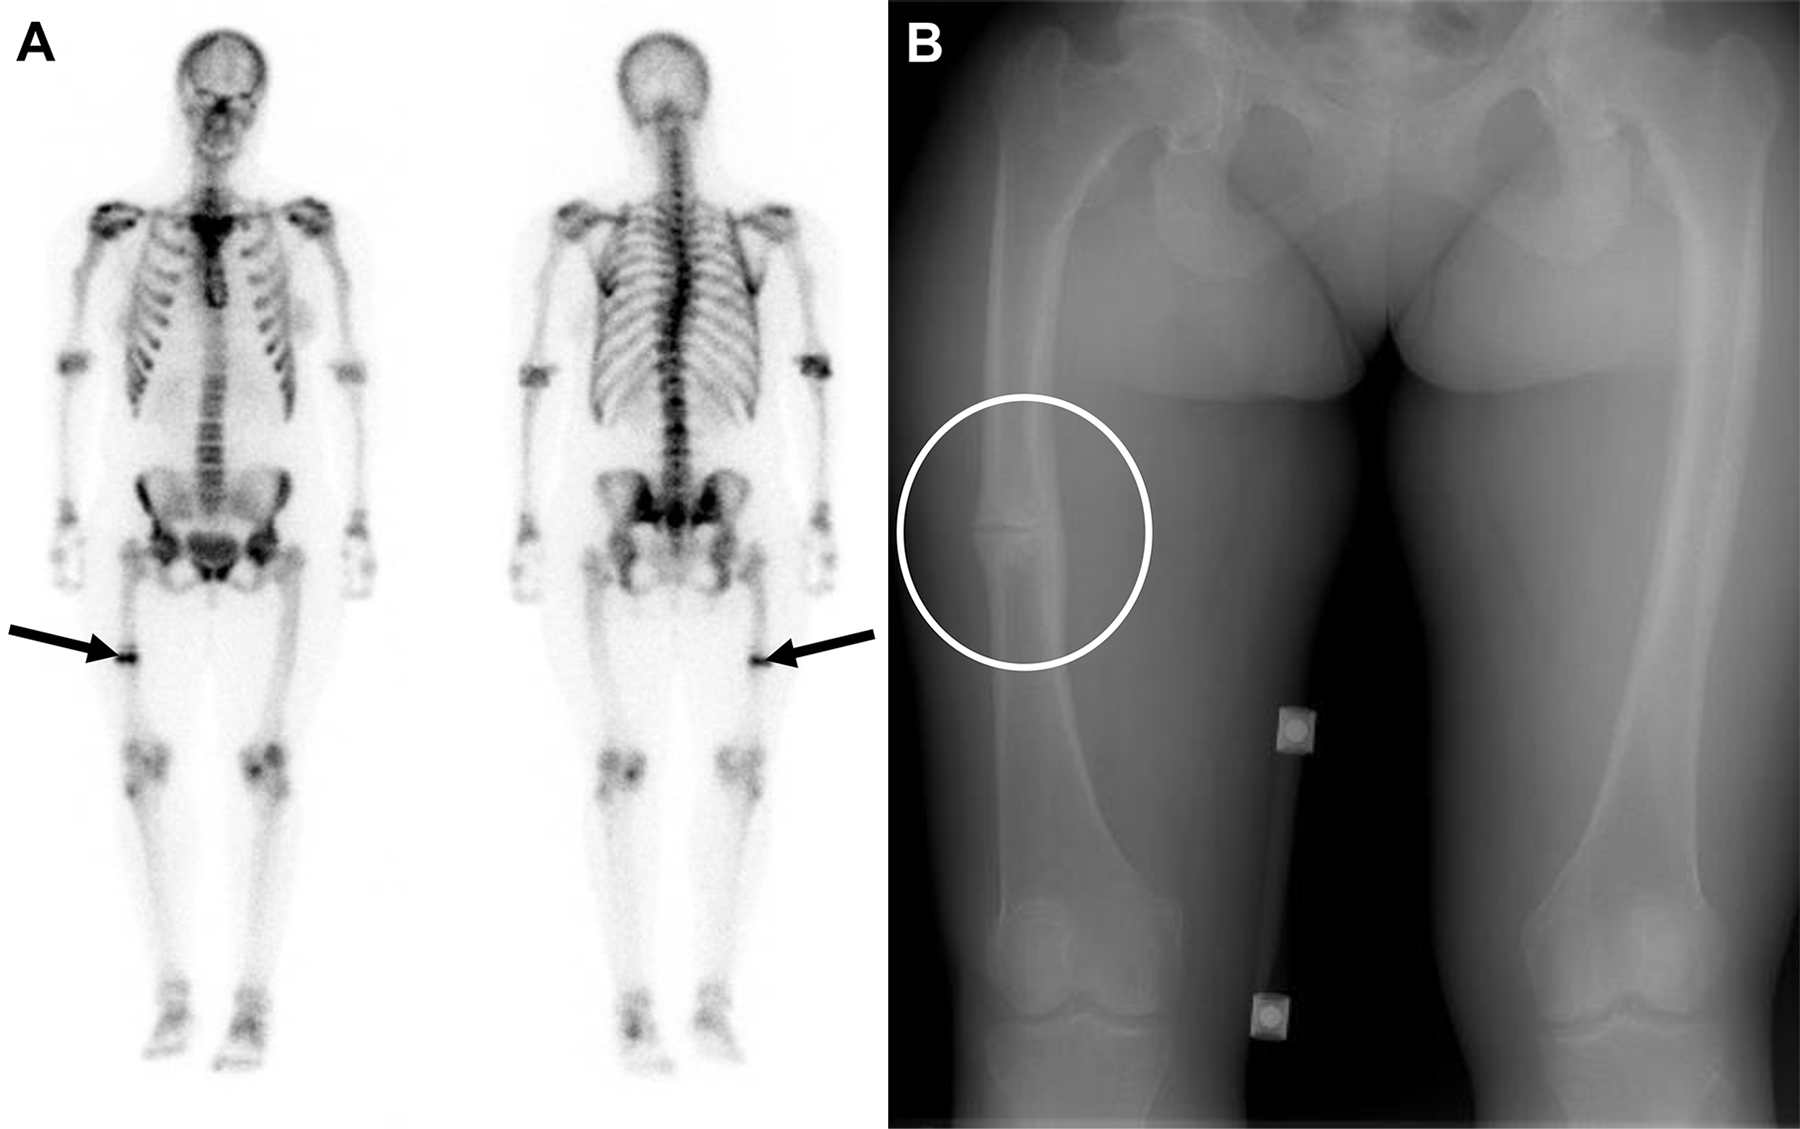

Ipofosfatemia legata all’X in una donna di 51 anni con dolore cronico alla gamba destra.

L’esame scintigrafico rileva una netta ipercaptazione focale a livello della porzione media della diafisi femorale destra. L’intensità e la localizzazione del reperto pongono il forte sospetto di un evento fratturativo.

L’imaging radiografico mirato conferma il sospetto metabolico-funzionale, documentando chiaramente l’interruzione della continuità ossea (frattura diafisaria) a carico del femore destro.

L’ipofosfatemia legata all’X è una malattia genetica rara che causa un’alterata e deficitaria mineralizzazione dell’osso. L’espressione clinica varia con l’età. Nell’età pediatrica si ha un quadro simil-rachitico, con svasamento delle metafisi (ex cartilagini di accrescimento) e deformità da carico degli arti inferiori (come il ginocchio varo). Nell’età adulta il difetto di mineralizzazione esita in osteomalacia, rendendo l’osso estremamente debole e predisponendo i pazienti a fratture patologiche, pseudofratture (le cosiddette strie o zone di Looser) e a una degenerazione osteoartrosica precoce.